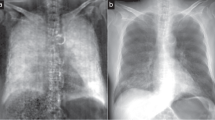

The acquired dark-field and attenuation radiographs are shown in Fig. 1.

Dark-field (top) and attenuation radiograph (bottom) images acquired with different tube voltages. A distinct decrease in dark-field signal strength can be seen towards higher tube voltages. At lower tube voltages, a higher opacity of bone is present in attenuation radiographs, impairing the visualization of the “lung”.